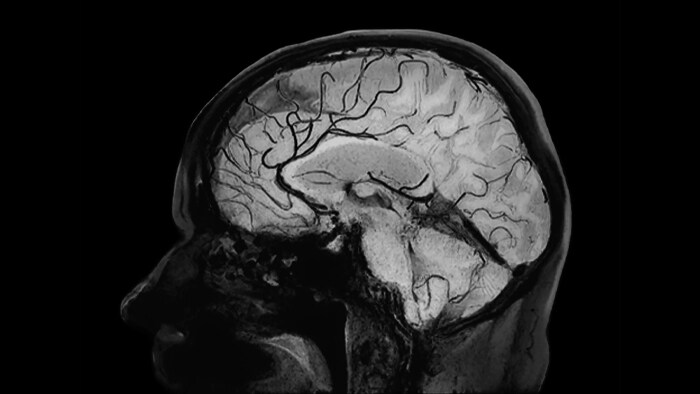

Black Blood imaging